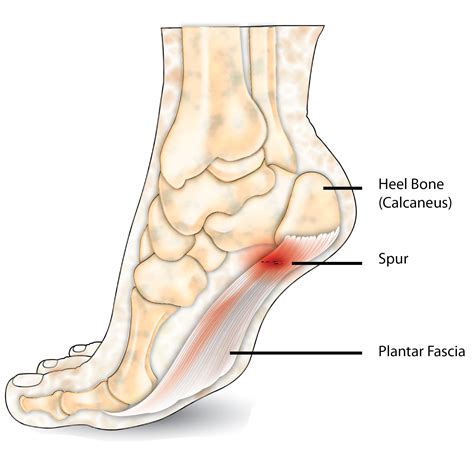

Foot spurs are calcium deposits that form on the underside of the heel bone. They are often associated with plantar fasciitis, a condition where the plantar fascia, a thick band of tissue that runs along the bottom of the foot, becomes inflamed. The inflammation can lead to the formation of a heel spur as the body attempts to repair the damaged tissue.

Visual aids can be incredibly helpful in understanding the condition. Below are some foot spurs pictures that illustrate the appearance and location of heel spurs:

This image shows a typical heel spur, highlighting the bony protrusion on the underside of the heel bone. The spur is often associated with plantar fasciitis, where the plantar fascia becomes inflamed and thickened.

Another example of a heel spur, this image provides a clearer view of the bony growth and its location on the heel. The spur can vary in size and shape, depending on the severity of the condition.